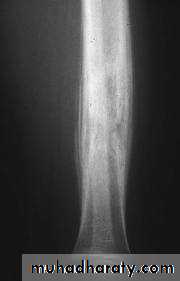

Plain x-ray

Show local sclerotic thickening of the shaft that may obscure the small central nidus within the area of rarefaction.The nidus is best seen on a fine cut CT scan

Intense uptake on an isotope bone scan.

Imaging13